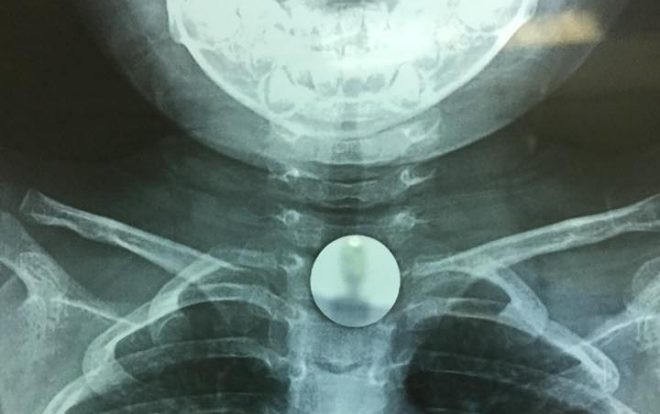

Hình ảnh đồng xu chắn ngang cuống họng bé K qua chụp Xquang.

Ngay khi tiếp nhận trường hợp của bé K, các bác sĩ bệnh viện đa khoa Đức Giang đã nhanh chóng chỉ định chụp phim Xquang vùng ngực - cổ để xác định vị trí dị vật. Hình ảnh Xquang cho thấy dị vật là một hình tròn giống đồng xu vị trí ngang giữa cổ. Dị vật mắc kẹt có cạnh tròn xung quanh nên không gây tổn thương niêm mạc.